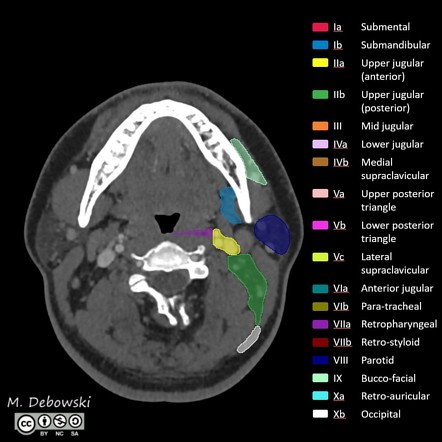

Image | Radiopaedia.org

radiopaedia.org

radiopaedia.org

radiopaedia lymph annotated axial